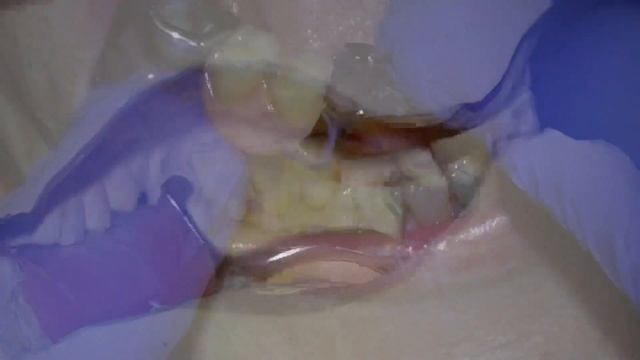

Fitting a Metal Based Chrome Cobalt Partial Denture смотреть онлайн

02:09

Fitting a Metal Based Chrome Cobalt Partial Denture